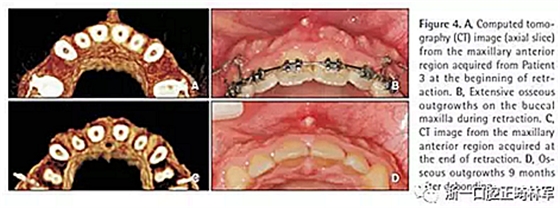

患者3

22歲,女性,主訴是牙齒不美觀?;颊叩那醒狼皟A,I類磨牙關(guān)系,深覆蓋,淺覆合。丙肝攜帶者,在接受疫苗接種。目標(biāo)是減小切牙前傾,獲得理想的覆合覆蓋,減少唇前突。治療計劃是拔除4顆前磨牙。

在這名患者觀察到最廣泛和嚴(yán)重的骨增生,且在第一個月最明顯。拆除托槽9個月后,這些增生明顯消退但仍舊很明顯(圖4)。內(nèi)收耗時11個月。